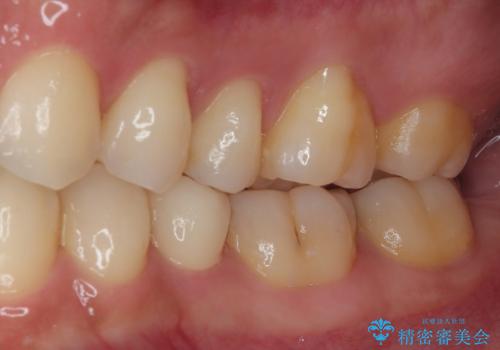

左下にフロスを通すと引っかかる オールセラミッククラウン

- 左下の奥歯のところがフロスが引っかかったり、ちぎれたりするとのことで来院された患者様です。検査の結果、神経は正常な反応を示し、フロスは引っかかる状態でしたので、虫歯治療も併せて行うためにオールセラミッククラウンによる補綴治療を行っていくことにしました。

フロスがちぎれることもなくなり、被せものが入っていることを忘れていたと大変喜んでいただきました。適合の良い被せものは二次的な虫歯の再発リスクを低減してくれます。